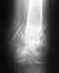

У меня вообщето была года четыре назад травма этой руки - кисть. Я падал в гололёд. Сейчас в июне получилось наложение на тренировке несколько раз резко махнул рукой. Мне 58, немного для себя занимаюсь спортом. Мнение спецалистов разошлось. Ставили диагноз перелом ладьевидной кости. Спецалист по кисти сказал выраженный артроз, старая травма, нужна операция - скреплять осколки спицей (?), операция на 21.01.2011. Затем травматологи сказали - операцию можно не делать, люди с этим живут всю жизнь. Теперь ещё непонятно - это перелом или артроз. До 2011 есть время и потом будет понятней. Что я смогу понять?

Снимки у меня на руках.